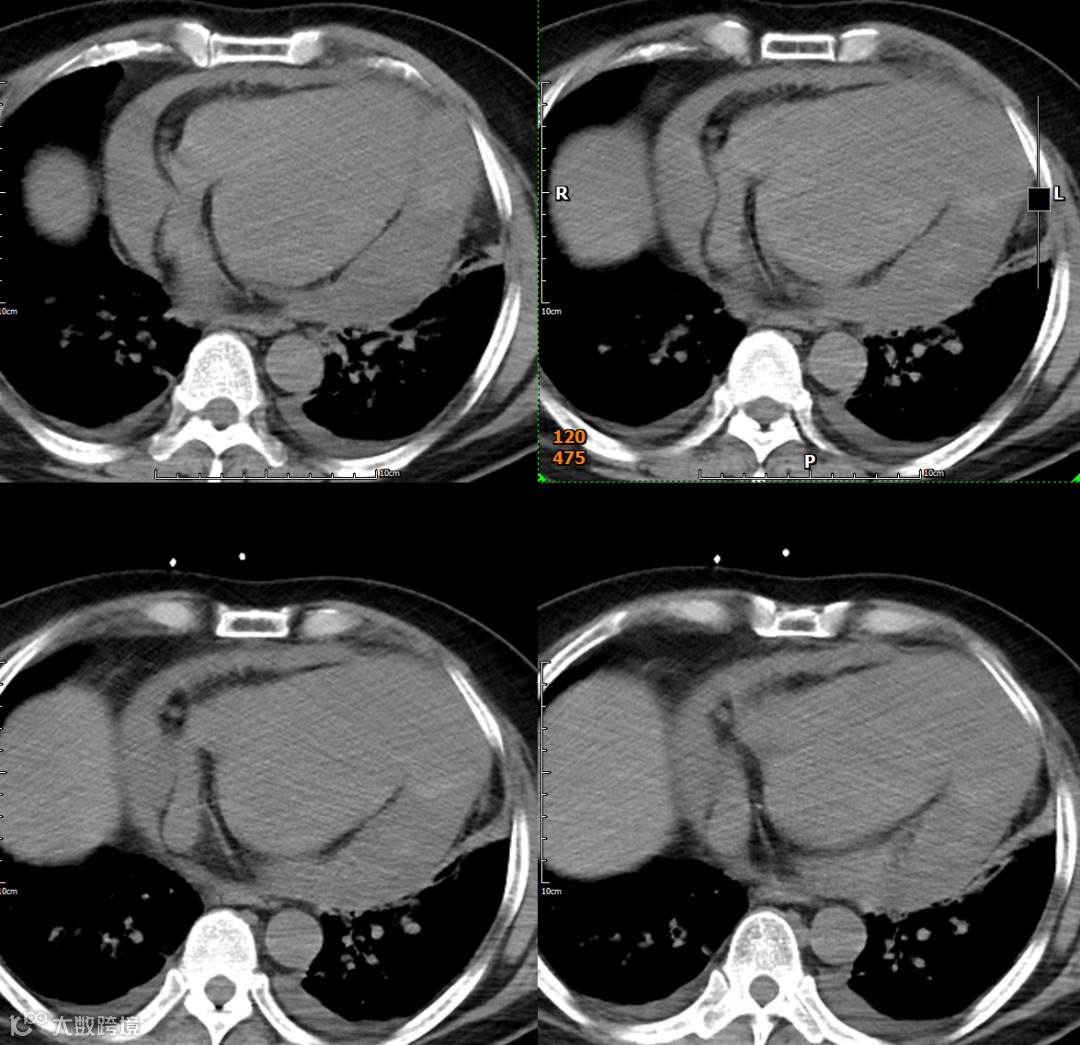

影像学检查

形态与位置:左心室局部囊状或宽基底向外膨出,常见于心尖部。膨出部分与左心室腔无明显界限。

瘤壁:变薄,但仍可见(虽然密度可能减低,提示纤维化)。CT可清晰显示瘤壁内(通常为心外膜下)或心腔内附壁血栓(低密度充盈缺损)。

瘤颈:宽大,与左心室腔自由交通。

形态与位置:与左心室腔相邻的囊状、球状或葫芦状对比剂充盈腔。特征性的窄瘤颈是其关键。位置常在心包反折附近(下壁、后壁、侧壁)。

瘤壁:菲薄,无心肌密度!主要由心包(可能钙化)和血栓(不强化或延迟强化)构成。

瘤颈:清晰可见的、狭窄的开口(如瓶颈状)将假性瘤腔与左心室腔相连。破口处心室壁中断是直接征象。

腔内:可见对比剂充盈,内常有血栓(充盈缺损)。

心包:局部心包增厚、粘连、积液常见。瘤体常部分嵌入心包内。